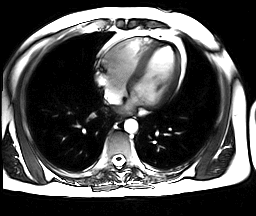

Método Doppler

Esta técnica utiliza ultra-som e o efeito Doppler para medir o débito cardíaco. A velocidade do sangue através da aorta causa um “desvio Doppler” na freqüência de retorno das ondas de ultra-som.

A medida pela ecocardiografia da superfície de corte do arco aórtico (ou, alternativamente, dá área da aorta descendente), combinada com a velocidade de fluxo, permite o cálculo do débito cardíaco.